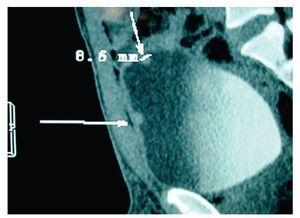

La nefrotomografía simple resultó muy dudosa a la presencia del cálculo referido en el ultrasonido anterior. El análisis general de orina reportó algunas bacterias, uno a dos eritrocitos por campo y huellas de proteínas. Se le solicitó URO-TAC, que demostró microlitiasis renal derecha del cáliz medio, no obstructivo, de aproximadamente tres milímetros. Además de pólipos vesicales múltiples (Imágenes 1 y 2).

Imagen 1. En el estudio de URO-TAC, a nivel vesical, las flechas señalan dos pequeñas tumoraciones; la de la cúpula vesical mide aproximadamente 8.6 mm.